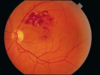

Macular degeneration

major cause of gradual, painless, bilateral central visual loss in the elderly; occurs in a nonexudative (dry) form and an exudative (wet) form